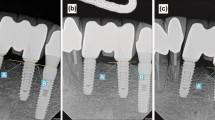

The evaluation of the vertical bone level (Table 4, Figure 3) was measured using a calibrated periodontal probe using the implant shoulder as starting point. At implant installation all implants were inserted epicrestally with the implant shoulder on the surrounding bone level. At implant uncovering the total value of pocket depth was 0.78 ±0.49 mm. After eight weeks an average of 1.31 ± 0.55 mm was found. 12 weeks after release of the implants for prosthetic loading, the average distance from implant shoulder to marginal bone was 1.46 ± 0.7 mm. It is to be noted that the bone loss was most prominent in mesial and distal regions with a mean of 1.5 mm mesially, and a mean of 1.55 mm distally (Table 4, Figure 4).

In addition to the analysis of implant stability, an additional emphasis of the presented study was the assessment of the marginal bone level in the area of implant shoulder. At implant uncovering the peri-implant bone status was measured using a calibrated parodontal probe at mesial, distal, buccal and oral sites. The average of the mean distances was 0.78 ± 0.49 mm at the time of implant uncovering. After 6 months this mean distance was 1.46 ± 0.7 mm. A loss of marginal periimplant bone of 0.68 mm after implant uncovering is comparable with the results by Ostman er al. [41], analyzing the marginal bone level at 257 implants.